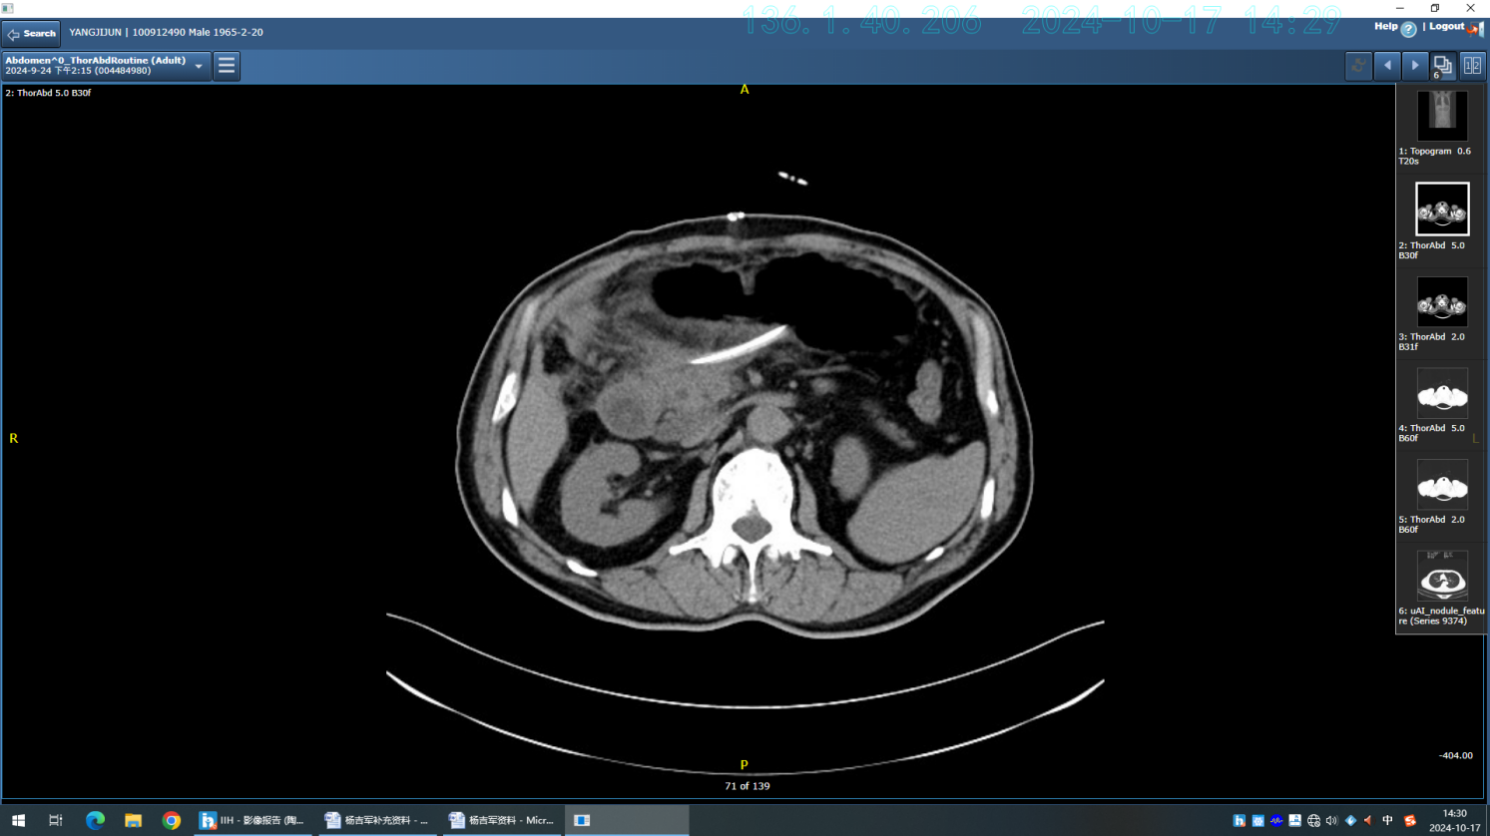

患者杨先生因“上腹部疼痛不适1月余”至扬州大学附属医院肝胆外科副主任、主任医师陶立德团队专家门诊就诊,查腹部CT结果检查结果示“胰头部占位”,予收住入院进一步诊治。入院后完善相关检查,认真评估患者肿瘤情况,考虑为胰腺神经内分泌肿瘤。

该患者肿瘤位于胰头部,治疗难度很大。扬大附院肝胆外科、影像科、麻醉科、消化内科、内分泌科等为其联合施行了多学科联合诊疗(MDT)。经术前精准评估,最终拟定两种手术方案进行比较选择:第一种方案是按传统手术方式施行保留幽门的胰十二指肠切除术,手术需切除十二指肠、部分胆总管、胆囊、胰头等,并完成胃肠、胰肠、胆肠等三处吻合,但该手术存在围手术期并发症多、患者术后会出现消化道功能障碍、营养不良等状况,影响生活质量,通常适用于预期生存期短的恶性肿瘤患者。第二种方案,施行胰头部分切除手术,即仅切除肿瘤及周围胰腺组织,术中完整保留胆管、十二指肠,避免胰管损伤,该方案优点在于在减少术中出血量、缩短手术时间、保护胰腺分泌功能等,预后远期效果优于前者。